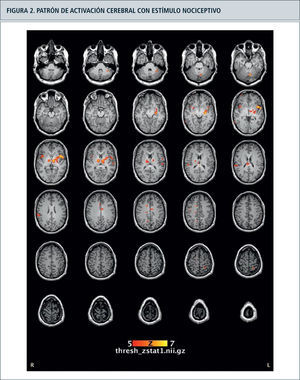

Bold-fMRICon la técnica de la resonancia magnética funcional dependiente del nivel de oxígeno sanguíneo (BOLD-fMRI) se detectan cambios de perfusión en zonas del cerebro entre 6–9 segundos después del inicio de la actividad neural. Así, esta técnica tiene una excelente resolución espacial, mas no temporal. Las aferencias nociceptivas se procesan en forma paralela en el cerebro a través de circuitos distribuidos, en lo que se ha conocido como la “matriz de dolor” (13). Esta matriz, en forma simple tiene un aspecto lateral discriminativo en la corteza sensorial primaria (S1) y secundaria (S2), tálamo y parte posterior de la ínsula y un aspecto medial afectivo-cognitivo, con la ínsula anterior, la corteza del cíngulo anterior y la corteza prefrontal (figura 2).

Resonancia magnética funcional con el registro de blood oxygen level-dependence (BOLD) en bloques de activación con estímulo de térmico de 50oC en el antebrazo derecho, con activación de la corteza somatosensitiva e insular contralateral. Asimismo se evidencia una activación del tálamo ipsi y contralateral. Estudio realizado en resonador GE 3 Teslas, Clínica Alemana en colaboración con el Sr. Francisco Zamorano (Centro de Investigación en Complejidad Social, UDD).